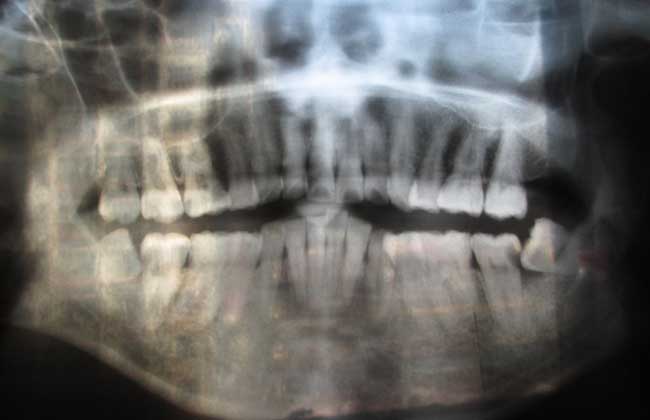

智齿的萌出时间很晚,通常在青春期萌出,而一个人在青春期的时候颌骨跟成年人的差不多了,所以没有足够的空间让智齿长出来,导致智齿的生长受到了限制,所以只能朝其他方向发展,或者是只长出一部分,又或者是全部都被埋在颌骨里面。又因为生长的空间受到了限制,所以智齿只能朝临近的牙齿生长,从而与第三颗磨牙产生了一个角度,并且会对第三颗磨牙造成挤压。

3、第二磨牙龋坏:向前倾斜的阻生智齿,因经常在邻牙间积存食物,易发生邻牙龋坏。